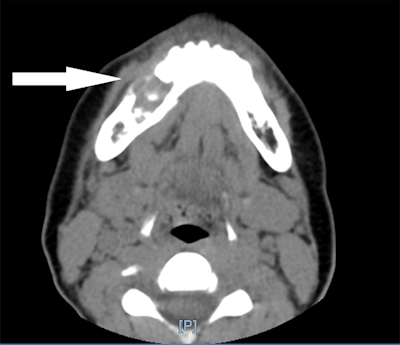

A computed tomography (CT) scan and histopathology results revealed a central giant cell granuloma centered in the right lower jaw with erosion of about 2.2 cm through the inner and outer cortex of the jaw. The patient made a full recovery after oral surgery, the authors wrote.

An oral surgery team was consulted, and a CT scan showed a lesion centered in the patient's right jaw with about 2.2 x 1.7 x 1.7 cm of erosion that went through the inner and outer cortex of the mandible. The erosion was centered on the roots of the right lower premolar teeth and first molar tooth with destruction of the second premolar tooth. This suggested a diagnosis of giant cell granuloma, and lab results from a biopsy sample confirmed it.